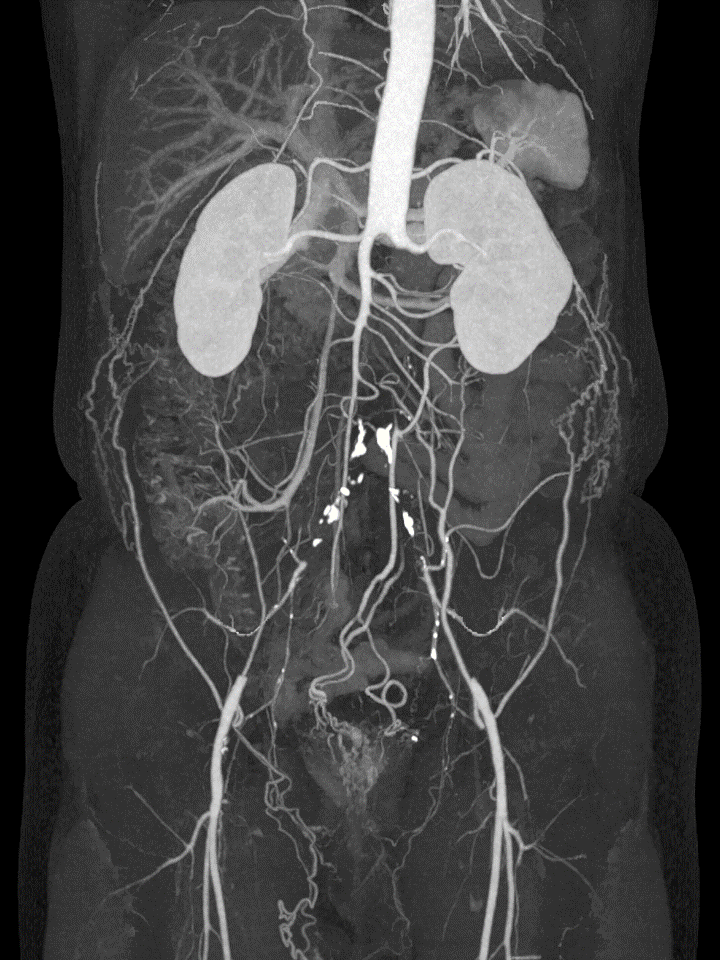

Leriche症候群は動脈硬化を主な要因とし、腹部大動脈下端から総腸骨動脈にかけて慢性の大動脈閉塞症を来たす疾患です。造影CTでは腎動脈以下の腹部大動脈本幹が描出されず、以下のような衝撃的な画像を示します。

本症の古典的な三徴は①間欠性跛行 ②下肢脈拍消失 ③勃起不全です。しかしながら本症では慢性的に発達した側副血行路により下肢や骨盤腔内臓器の血流が維持されており、派手な画像所見に比べると症状は軽微であったり無症候性であることも珍しくありません。そのため本症の診断には身体所見が診断の大きな手掛かりになりえます。間欠性跛行を示す疾患はほかにASOや腰部脊柱管狭窄症などが挙がりますが、Leriche症候群を忘れないようにしましょう。両下肢の動脈触知を丁寧に行い、脈拍だけではなく「左右差」を評価することも必要です。

前述のように本症の原因は動脈硬化に起因するものが多数を占め、冠動脈疾患や腎機能障害を併う場合があることから併存疾患の検索が重要です。特に虚血性心疾患の合併が目立つことから、心機能や冠動脈の評価を行いましょう。

足趾の血流障害が強い、あるいは間欠性跛行の増悪が著しい症例に対しては外科的にバイパス術を行います。また内服療法としてはシロスタゾールやアスピリンなどの抗血小板薬が推奨されています。